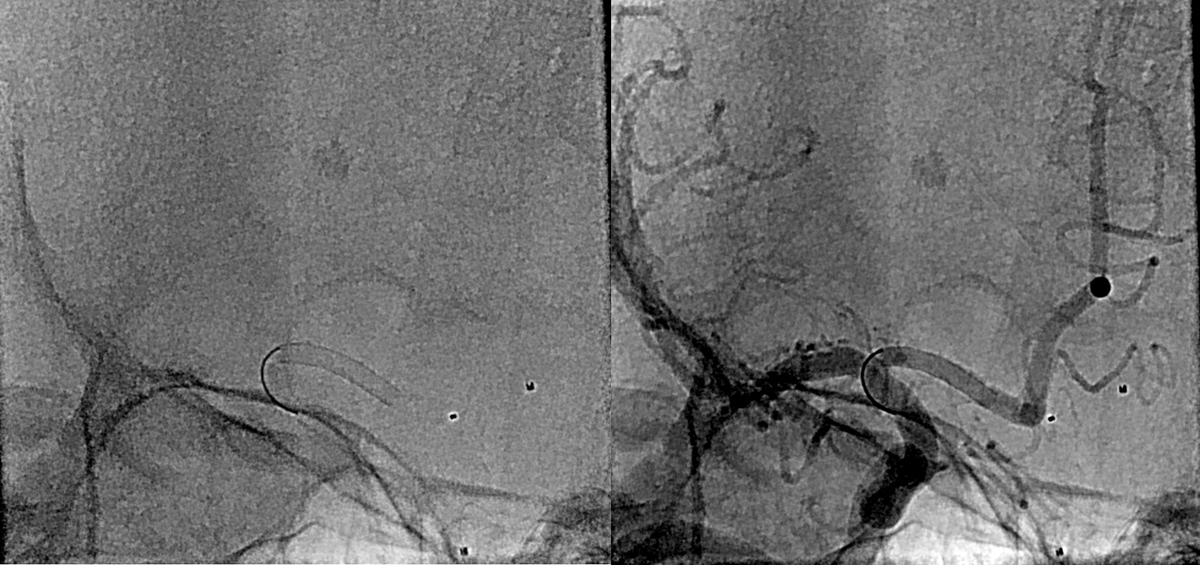

@Radhey2006 @ISVIRIndia @JVIRmedia @SIRspecialists @SIRRFS @cirsesociety @ApolloHosMumbai Used varying injections bet 25-66%. Yes managing migration was bit tricky but could manage with pressure control, controlled injection

@MumbaiIR @ISVIRIndia @JVIRmedia @SIRspecialists @SIRRFS @cirsesociety @ApolloHosMumbai Sir what percentage of glue used seems very high flow and how u prevent migration into vein ?

Case : AVM of leg with Pain & Limp.

Rx : AVM Embolization with Glue

#avm #embolization #irad #interventionalradiology #MedTwitter #Mumbai @ISVIRIndia @JVIRmedia @SIRspecialists @SIRRFS @cirsesociety @ApolloHosMumbai